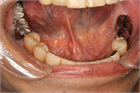

1. 唾石に伴う口底の発赤、腫脹および疼痛がある場合、抗生剤、抗炎症鎮痛剤を投与することが推奨される(推奨度1)

1. 導管内に限局し比較的小さいものでは唾液腺マッサージし自然排出を促すことが推奨される(推奨度2)